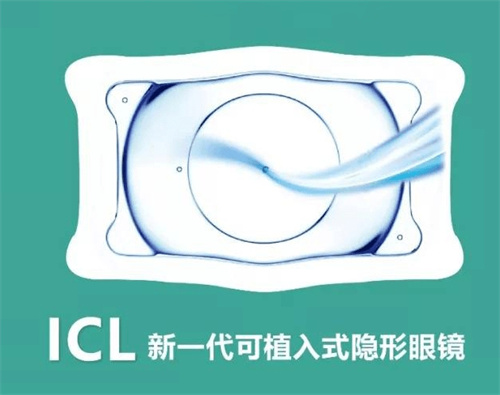

首先,需要明确的是,高度近视1500度并非手术的肯定禁忌。在医学技术不断发展的今天,有多种手术方式可以考虑用于矫正高度近视。其中,眼内屈光手术,特别是人工晶体植入术(ICL),被认为是针对高度乃至***度近视患者的有效选择。

人工晶体植入术(ICL)通过在眼内植入一个特殊的人工晶体来矫正视力,这种手术避免了切削角膜的风险,且对角膜厚度没有严格要求。对于近视度数高达1500度的患者来说,这种手术方式可能更为适合。ICL手术适应的近视度数范围广泛,通常可矫正300度到2300度的近视,以及600度以下的散光。